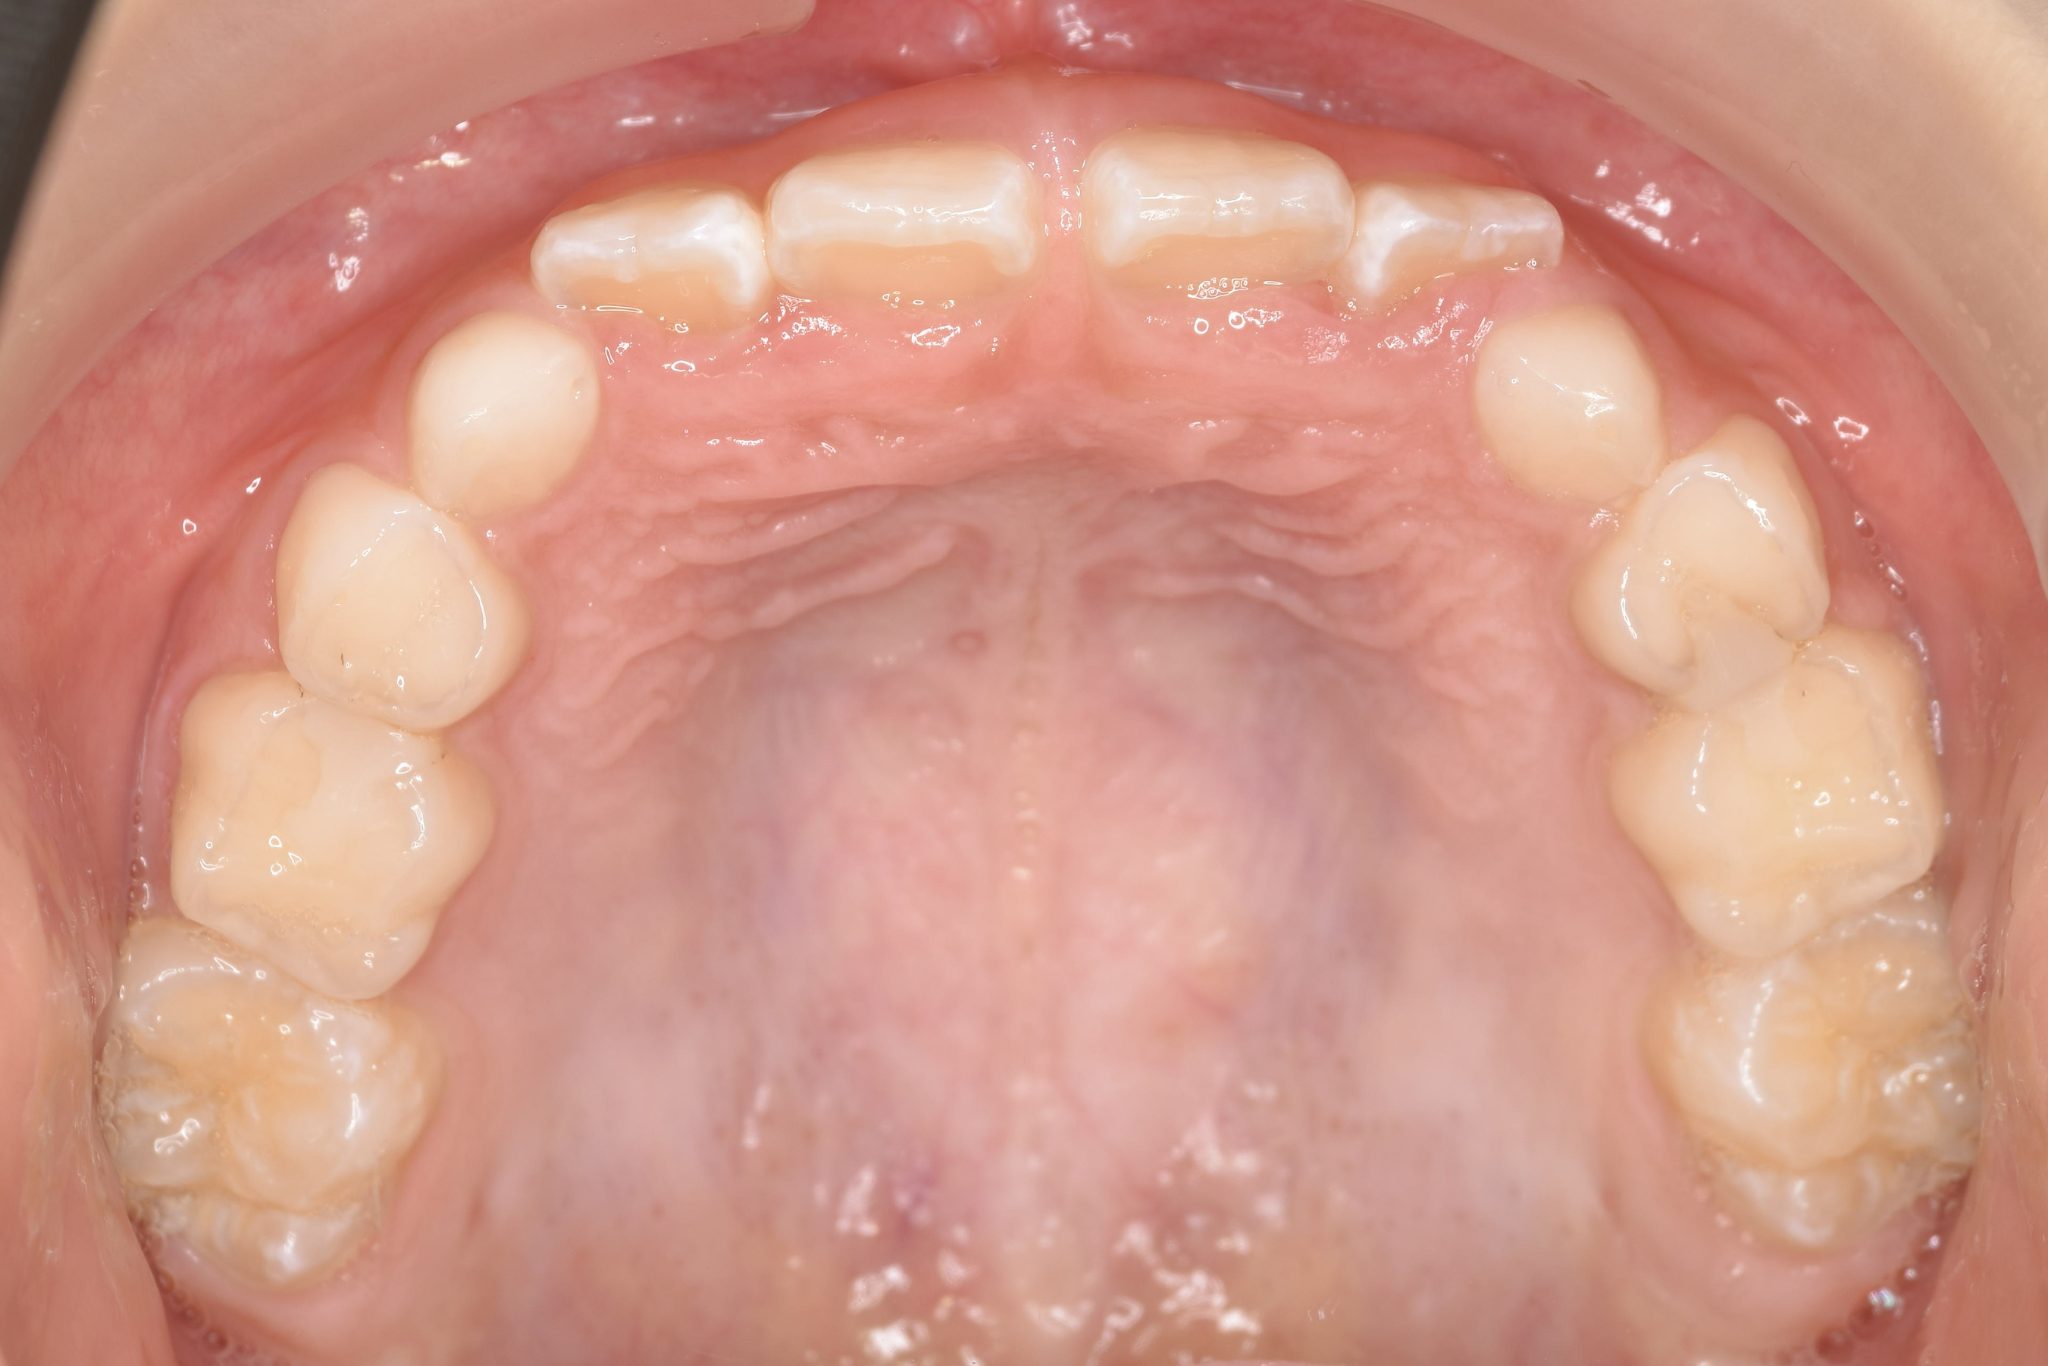

アフター

子どもの矯正治療|症例_858

施術内容 上顎急速拡大装置と下顎リンガルアーチを用いて上下顎骨を拡大した。

上顎前方牽引装置を用いて上顎骨を前方に成長促進させた。

その後マウスピース型矯正装置で歯牙を配列し良好な咬合を獲得した。

治癒期間 1年6か月 ※経過観察含む